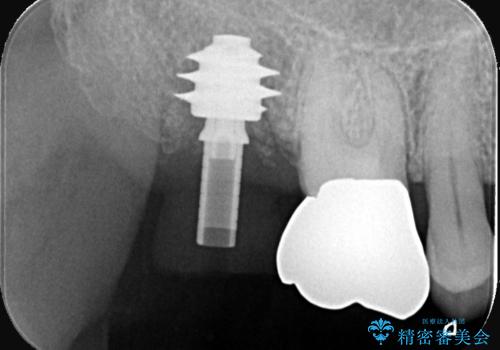

抜歯即時インプラント|切開しないので低侵襲治療|痛く無い治療!

- 当院にて根管治療を行いましたが、病変の改善が得られなかったため、インプラント治療を行う方針といたしました。

抜歯即時埋入の適応と判断し、抜歯当日にインプラント埋入を行う「抜歯即時埋入」にて処置を実施しました。

抜歯即時インプラントの利点(共振周波数解析を用いたISQ値の測定により、客観的かつ数値でインプラントの安定性を評価できるようになったため、予知性が高く安全な治療となった。)

抜歯とインプラント埋入を同時に行うため、抜歯窩の治癒を待つ必要がなく、全体の治療期間を短縮できる。

抜歯後は速やかに歯槽骨の吸収が進むが、即時にインプラントを埋入することで骨吸収を抑制できる。